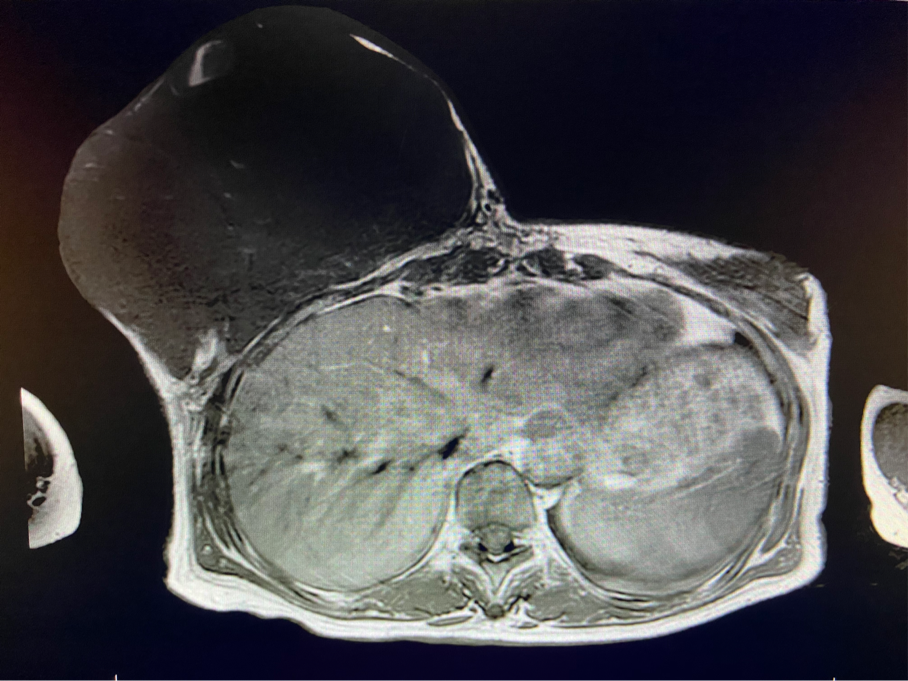

王女士終于可以暢快呼吸、正常走路了,不用再擔(dān)心壓在胸前令人窒息的腫瘤和別人異樣的眼光。近日,王女士在西安國(guó)際醫(yī)學(xué)中心醫(yī)院甲乳外科接受了右乳全乳切除術(shù) 胸壁皮瓣成形術(shù)或植皮術(shù),切除了胸口重達(dá)5斤的腫瘤。

6個(gè)月前,王女士能感覺(jué)到右乳腫物明顯增大至“鴨蛋”一般,而且伴有局部皮膚瘙癢及輕度脹痛,可這次王女士并沒(méi)有那么幸運(yùn),服藥3個(gè)月不僅沒(méi)有控制住腫物,脹痛也越發(fā)嚴(yán)重,超聲檢查提示:右乳囊實(shí)性占位,最大前后徑約10.8cm,右腋窩多發(fā)腫大淋巴結(jié),遂行右乳腫物穿刺活檢術(shù),術(shù)后病理檢查提示:右乳腫物穿刺乳腺組織2條,均可見(jiàn)導(dǎo)管囊性擴(kuò)張,部分區(qū)域間質(zhì)纖維增生,其中1條內(nèi)導(dǎo)管上皮成普通型增生。輾轉(zhuǎn)當(dāng)?shù)囟嗉裔t(yī)院藥物治療后,錢沒(méi)有少花,但是療效甚微。

2周前,王女士的右乳外下方皮膚破潰,伴大量滲液,還發(fā)出陣陣惡臭。經(jīng)多方打聽(tīng),王女士從外地來(lái)到西安國(guó)際醫(yī)學(xué)中心醫(yī)院甲乳外科劉曉敏主任處就診。入院后,迅速完善了一系列相關(guān)術(shù)前檢查:王女士的雙乳外形不對(duì)稱,右乳約22?20cm,皮膚水腫明顯并可見(jiàn)靜脈曲張。右乳外下象限皮膚可見(jiàn)局部破潰,創(chuàng)面有3處,共約6?4cm大小,創(chuàng)面呈暗紅色,伴有血性滲出及惡臭,局部皮膚溫度升高。右側(cè)腋窩可觸及腫大淋巴結(jié)。

該患者右乳巨大腫物術(shù)前初步考慮乳腺葉狀腫瘤可能,因腫瘤太大,幾乎遍及整個(gè)右側(cè)乳房,為保證“無(wú)瘤原則”,術(shù)中切除范圍位置未知,極有可能出現(xiàn)皮瓣缺損。于是,經(jīng)過(guò)和整形醫(yī)院郭樹(shù)忠院長(zhǎng)、整形外科王愛(ài)武主任的討論,提供了兩種手術(shù)方式,一是創(chuàng)面修復(fù)(植皮或轉(zhuǎn)移皮瓣修復(fù)創(chuàng)面),二是乳房再造,與患者及家屬溝通后,決定先解決腫物,3年病情不再?gòu)?fù)發(fā)后,可以再考慮乳房重建。